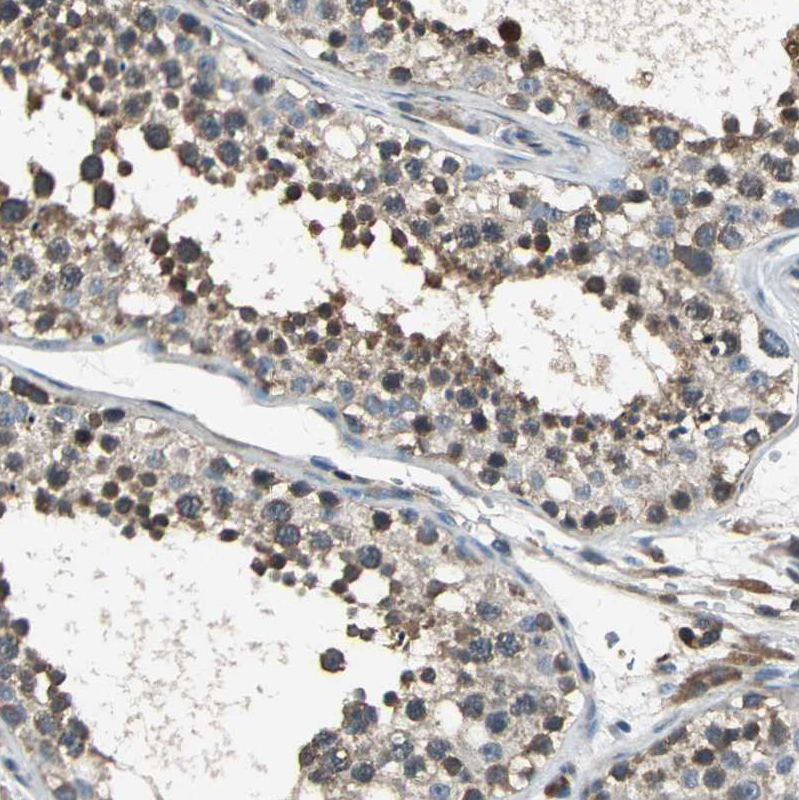

Immunohistochemistry analysis in human thyroid gland and liver tissues using HPA005841 antibody. Corresponding EIF2B2 RNA-seq data are presented for the same tissues.